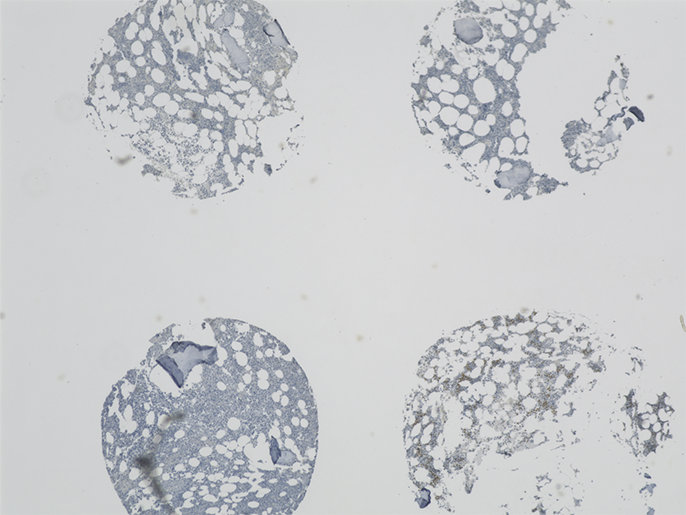

Eine Besonderheit der Arbeitsgruppe sind die eigens entwickelten Tissue Microarrays (TMAs) von MDS-Knochenmark-Stanzbiopsien, auf denen zum direkten Vergleich auch Biopsien von Patienten mit AML (akute myeloische Leukämie) sowie normale Kontrollen enthalten sind. Für die Auswertung von immunhistochemischen Untersuchungen an den TMAs ist ein großer Vorteil des Fluoreszenzmikroskops BZ, dass eine – oder sogar mehrere – Proben auf dem TMA zusammenhängend in einem Bild erfasst werden können.

„Die Stitching-Funktion ist dabei für uns besonders wichtig, um den 2 mm großen Core in einem Bild darstellen zu können“, erklärt Norbert Gattermann.